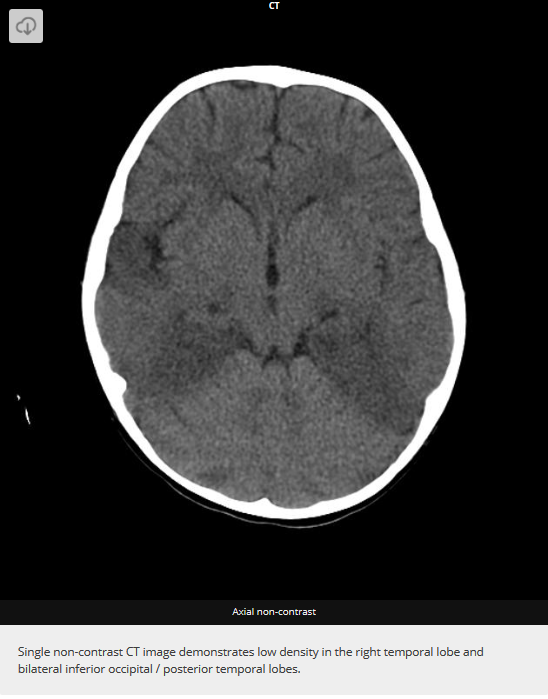

HSV1 classically affects temporal and inferior frontal lobes